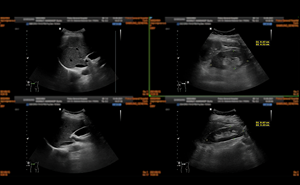

Acute Mitral Regurgitation in the Emergency Department

A 56-year-old female with history of hyperlipidemia, mild mitral regurgitation, and type 2 diabetes presents to the emergency department for 5 days of diffuse chest pain with dyspnea, lower extremity ...